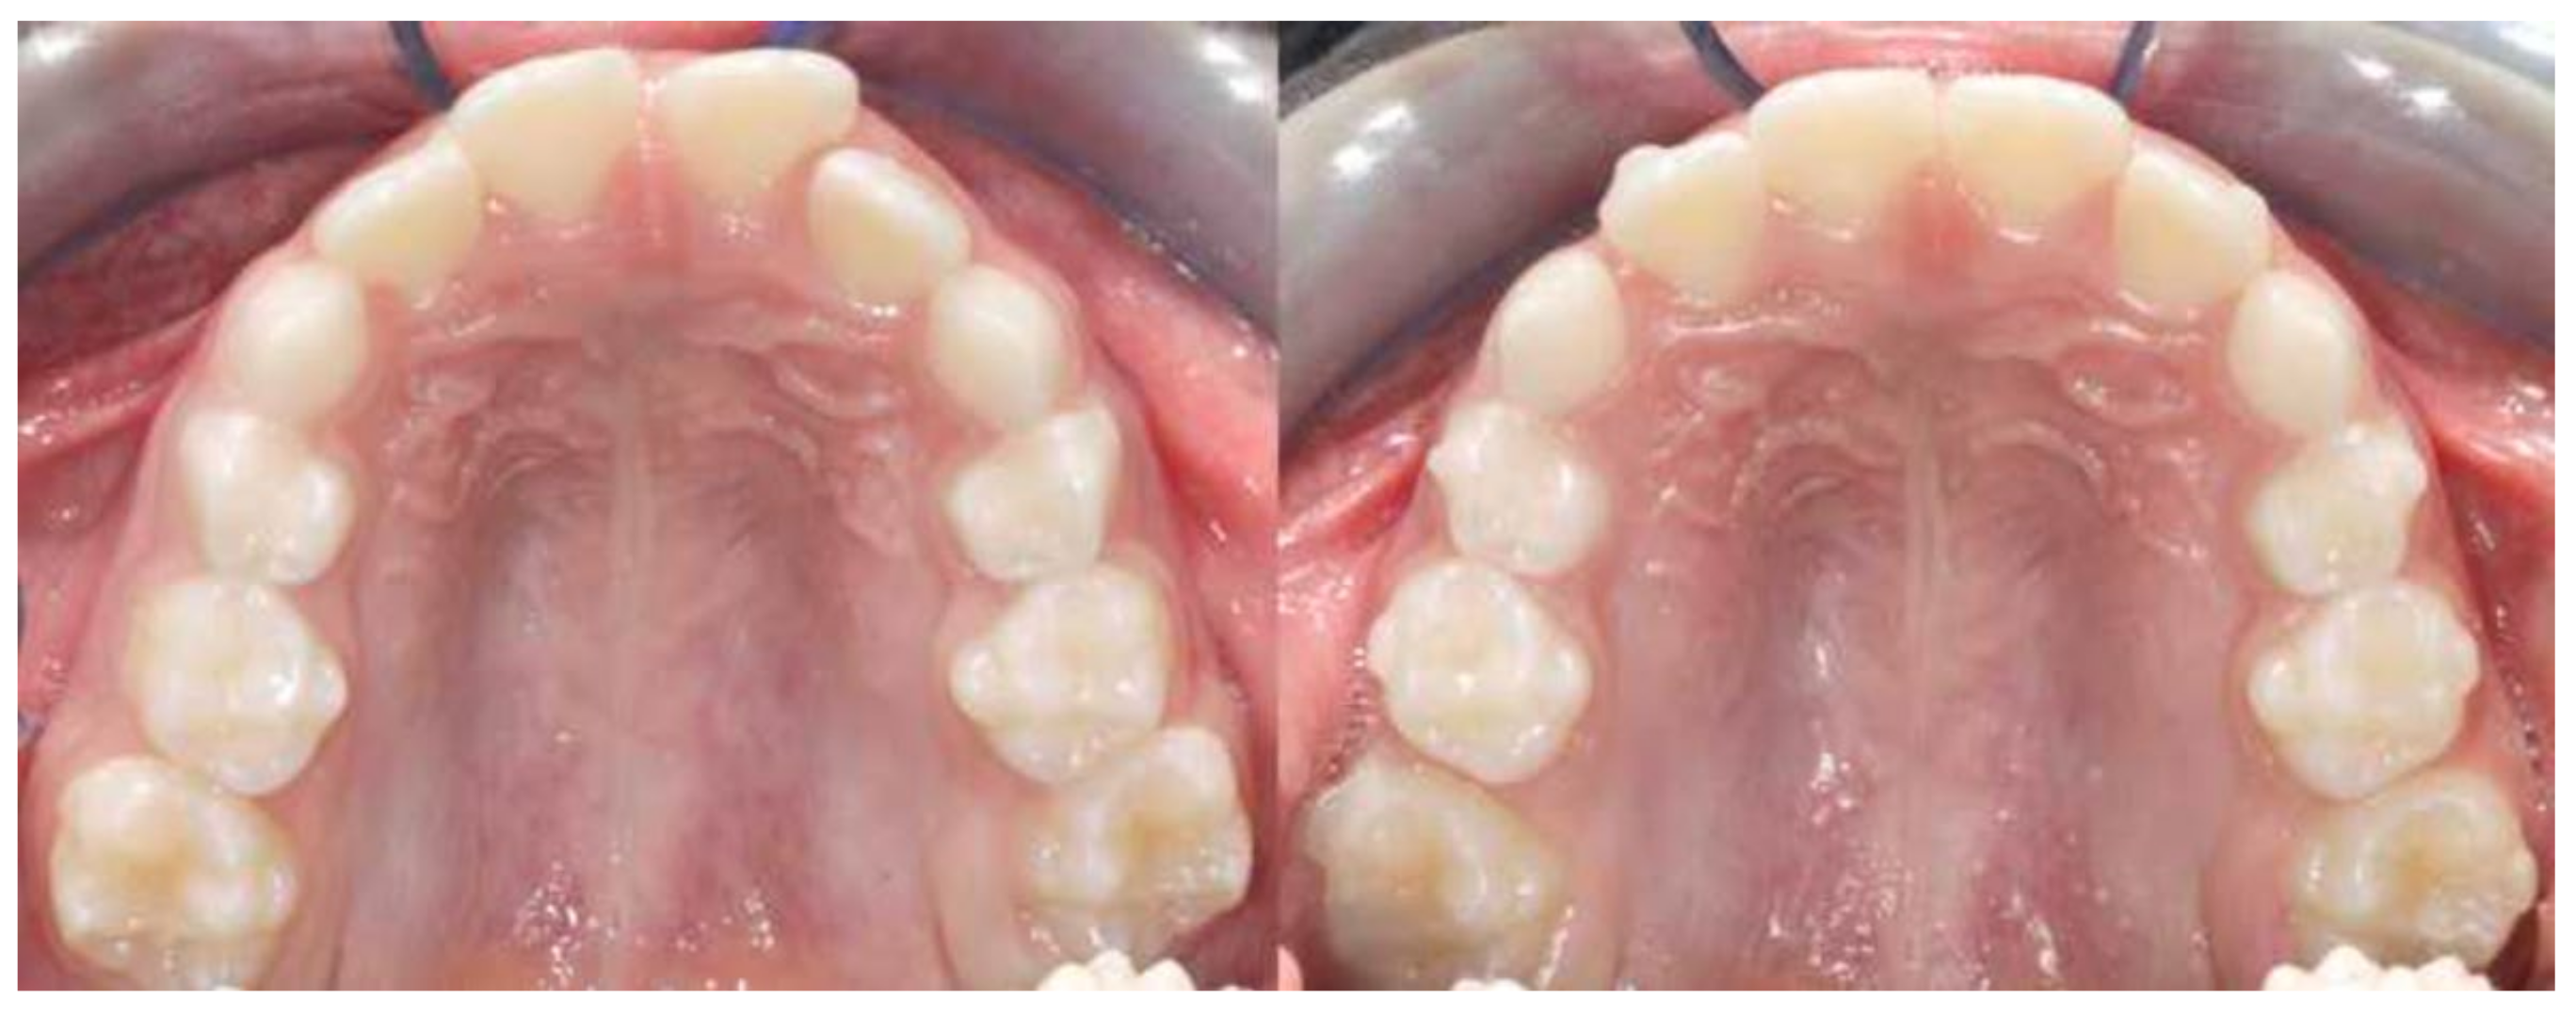

Figure 3. Intraoral occlusal evaluation pre-treatment (T1) and post-treatment (T2).

Our results showed that there were statistically significant differences between T2-T1 maxillary first molar rotation (Figure 3). In the present study, the upper molars were mildly mesial rotated since the study group involved was in mixed dentition, before the exfoliation of second deciduous molars, and with a Class II edge-to-edge malocclusion. This meant that our treatment protocol required molar disto-rotation without distalization. The main derotation observed was of about six degrees. Giuntini et al. [8] reported that in the case of extreme mesial rotation of the upper permanent molar, i.e., when the molar is included in the dental arch perimeter with its oblique diameter instead of its mesiodistal diameter, maximal molar derotation leads to a corresponding maximal gain of space of about 2.5 mm. According to our results, orthodontic molar derotation (about six degrees) led to a mean gain of arch space of about 1 mm. Our findings agree with Braun et al. [12], who reported a value of gain in arch perimeter of 2.5 mm with an upper molar derotation of about 20 degrees. It is important to emphasize that the gain in arch perimeter following molar derotation occurred anteriorly to the derotated tooth, as the buccal cusps moved distally by about 1 mm, with a simultaneous improvement in the molar occlusal relationship.